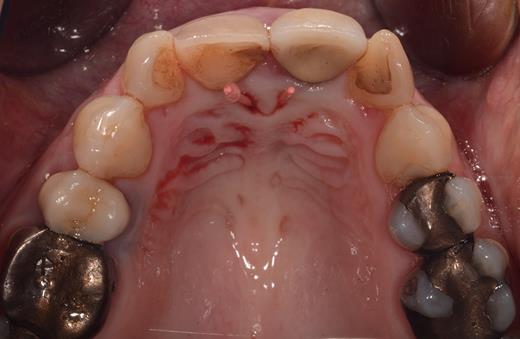

Clinical examination revealed two small mucosal openings on either side of the incisive papilla, which could be probed partially (Fig. 1). Palpation of this area was painful. Two gutta-percha points were inserted into the two openings (Fig. 2). The cone beam computed tomography (CT) confirmed two patent NDPs with oronasal communication (Fig. 3).

Preoperative clinical situation: occlusal view of the maxillary arch presenting two small depressions of the mucosa on either side of the incisive papilla (blue arrows).